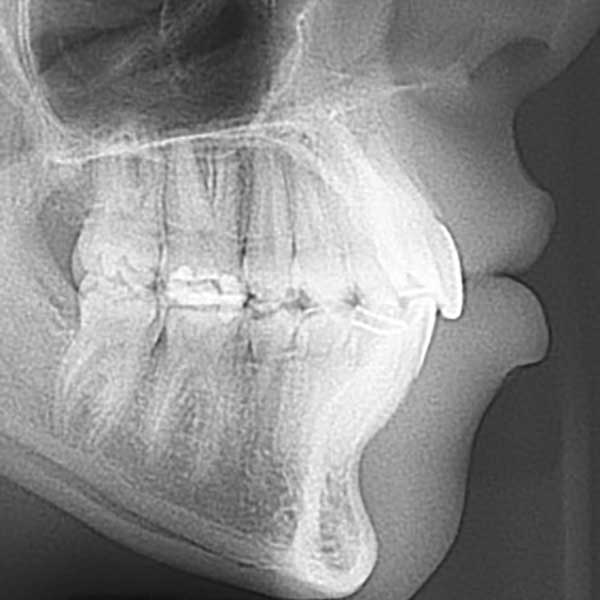

AFTER

بعد الفحص الدقيق، وجد الدكتور خالد الكاتب أن الأسنان العلوية متقدمة على السفلية بمسافة كبيرة (8 مم)، وأن السبب الجذري للمشكلة هو تراجع الفك السفلي. ونظراً لصغر عمر المراجعة ورفض الأهل لخيار قلع الأسنان، تم وضع خطة علاج ذكية تعتمد على تقديم الفك السفلي للأمام باستخدام جهاز وظيفي ثابت، وهو خيار مثالي في مرحلة النمو.

كما تظهر الصور، تم تصحيح مشكلة البروز بالكامل. تقدم الفك السفلي إلى وضعه الصحيح، مما أدى إلى تناسق رائع في ملامح الوجه وإطباق مثالي للأسنان. الأهم من ذلك، استعادت صديقتنا الصغيرة ابتسامتها المشرقة وثقتها بنفسها.